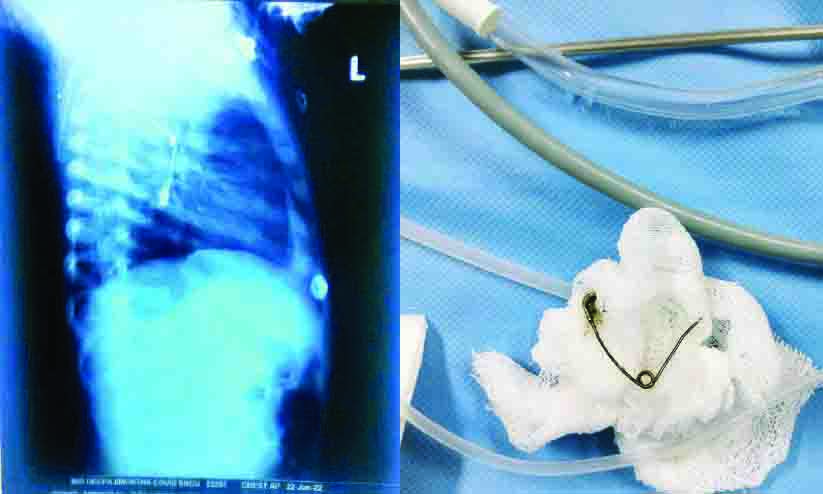

text_fields1. കുഞ്ഞിന്റെ വയറ്റിൽ സ്കാനിങ്ങിൽ കണ്ട സേഫ്റ്റി പിൻ 2. പുറത്തെടുത്ത സേഫ്റ്റി പിൻ

മുളങ്കുന്നത്തുകാവ്: ഗവ. മെഡിക്കൽ കോളജിൽ എട്ടു മാസം പ്രായമുള്ള ആൺകുഞ്ഞിന്റെ അന്നനാളത്തിൽ കുടുങ്ങിയ സേഫ്റ്റി പിൻ വിദഗ്ധമായി പുറത്തെടുത്തു. ബ്രോങ്കോസ്കോപി ചെയ്താണ് പുറത്തെടുത്തത്.

മണ്ണുത്തി വല്ലച്ചിറ ദീപയുടെ കുഞ്ഞിന് അന്നനാളം, ശ്വാസകോശം, തലച്ചോറ് എന്നിവക്ക് അസുഖം ബാധിച്ചാണ് ജനുവരി 19ന് ജില്ല ജനറൽ ആശുപത്രിയിൽനിന്ന് മെഡിക്കൽ കോളജിൽ പ്രവേശിപ്പിച്ചത്. തലച്ചോറിെൻറ പ്രവർത്തനം തകരാറിലായതിനെ തുടർന്ന് വെൻറിലേറ്ററിൽ പ്രവേശിപ്പിച്ചു. പരിശോധനയിൽ തലച്ചോറിൽ പഴുപ്പ് കണ്ടെത്തി. അതിനിടെ കുഞ്ഞ് കോവിഡ് പോസിറ്റിവായി. പിന്നീട് നടത്തിയ പരിശോധനയിലാണ് അന്നനാളത്തിൽ സേഫ്റ്റി പിൻ കുത്തി ശ്വാസകോശത്തിലും പഴുപ്പ് ബാധിച്ചതായി കണ്ടത്.

ശിശുരോഗ ശസ്ത്രക്രിയ വിഭാഗം പിൻ വിജയകരമായി പുറത്തെടുത്തു. മൂന്നാഴ്ച കഴിഞ്ഞ് കുഞ്ഞിെൻറ ആരോഗ്യനിലയിൽ പുരോഗതി ഉണ്ടായതിനെ തുടർന്ന് വെൻറിലേറ്ററിൽനിന്ന് മാറ്റി. ഡോക്ടർമാരായ ടി.എ. ഷീല, ദീപ അനിരുദ്ധൻ എന്നിവരുടെ നേതൃത്വത്തിൽ നിരീക്ഷണത്തിലാണ് കുഞ്ഞ്. ന്യൂറോ സർജറി വിഭാഗം മേധാവി ഡോ. ബിജു കൃഷ്ണെൻറ നേതൃത്വത്തിൽ ഡോ. ജിയോ സനിൽ, ഡോ. ജിതിൻ, ഡോ. ആമോൾ, ഡോ. ഷാഹിദ എന്നിവർ സംയുക്ത സംരംഭത്തിൽ പങ്കാളികളായി.